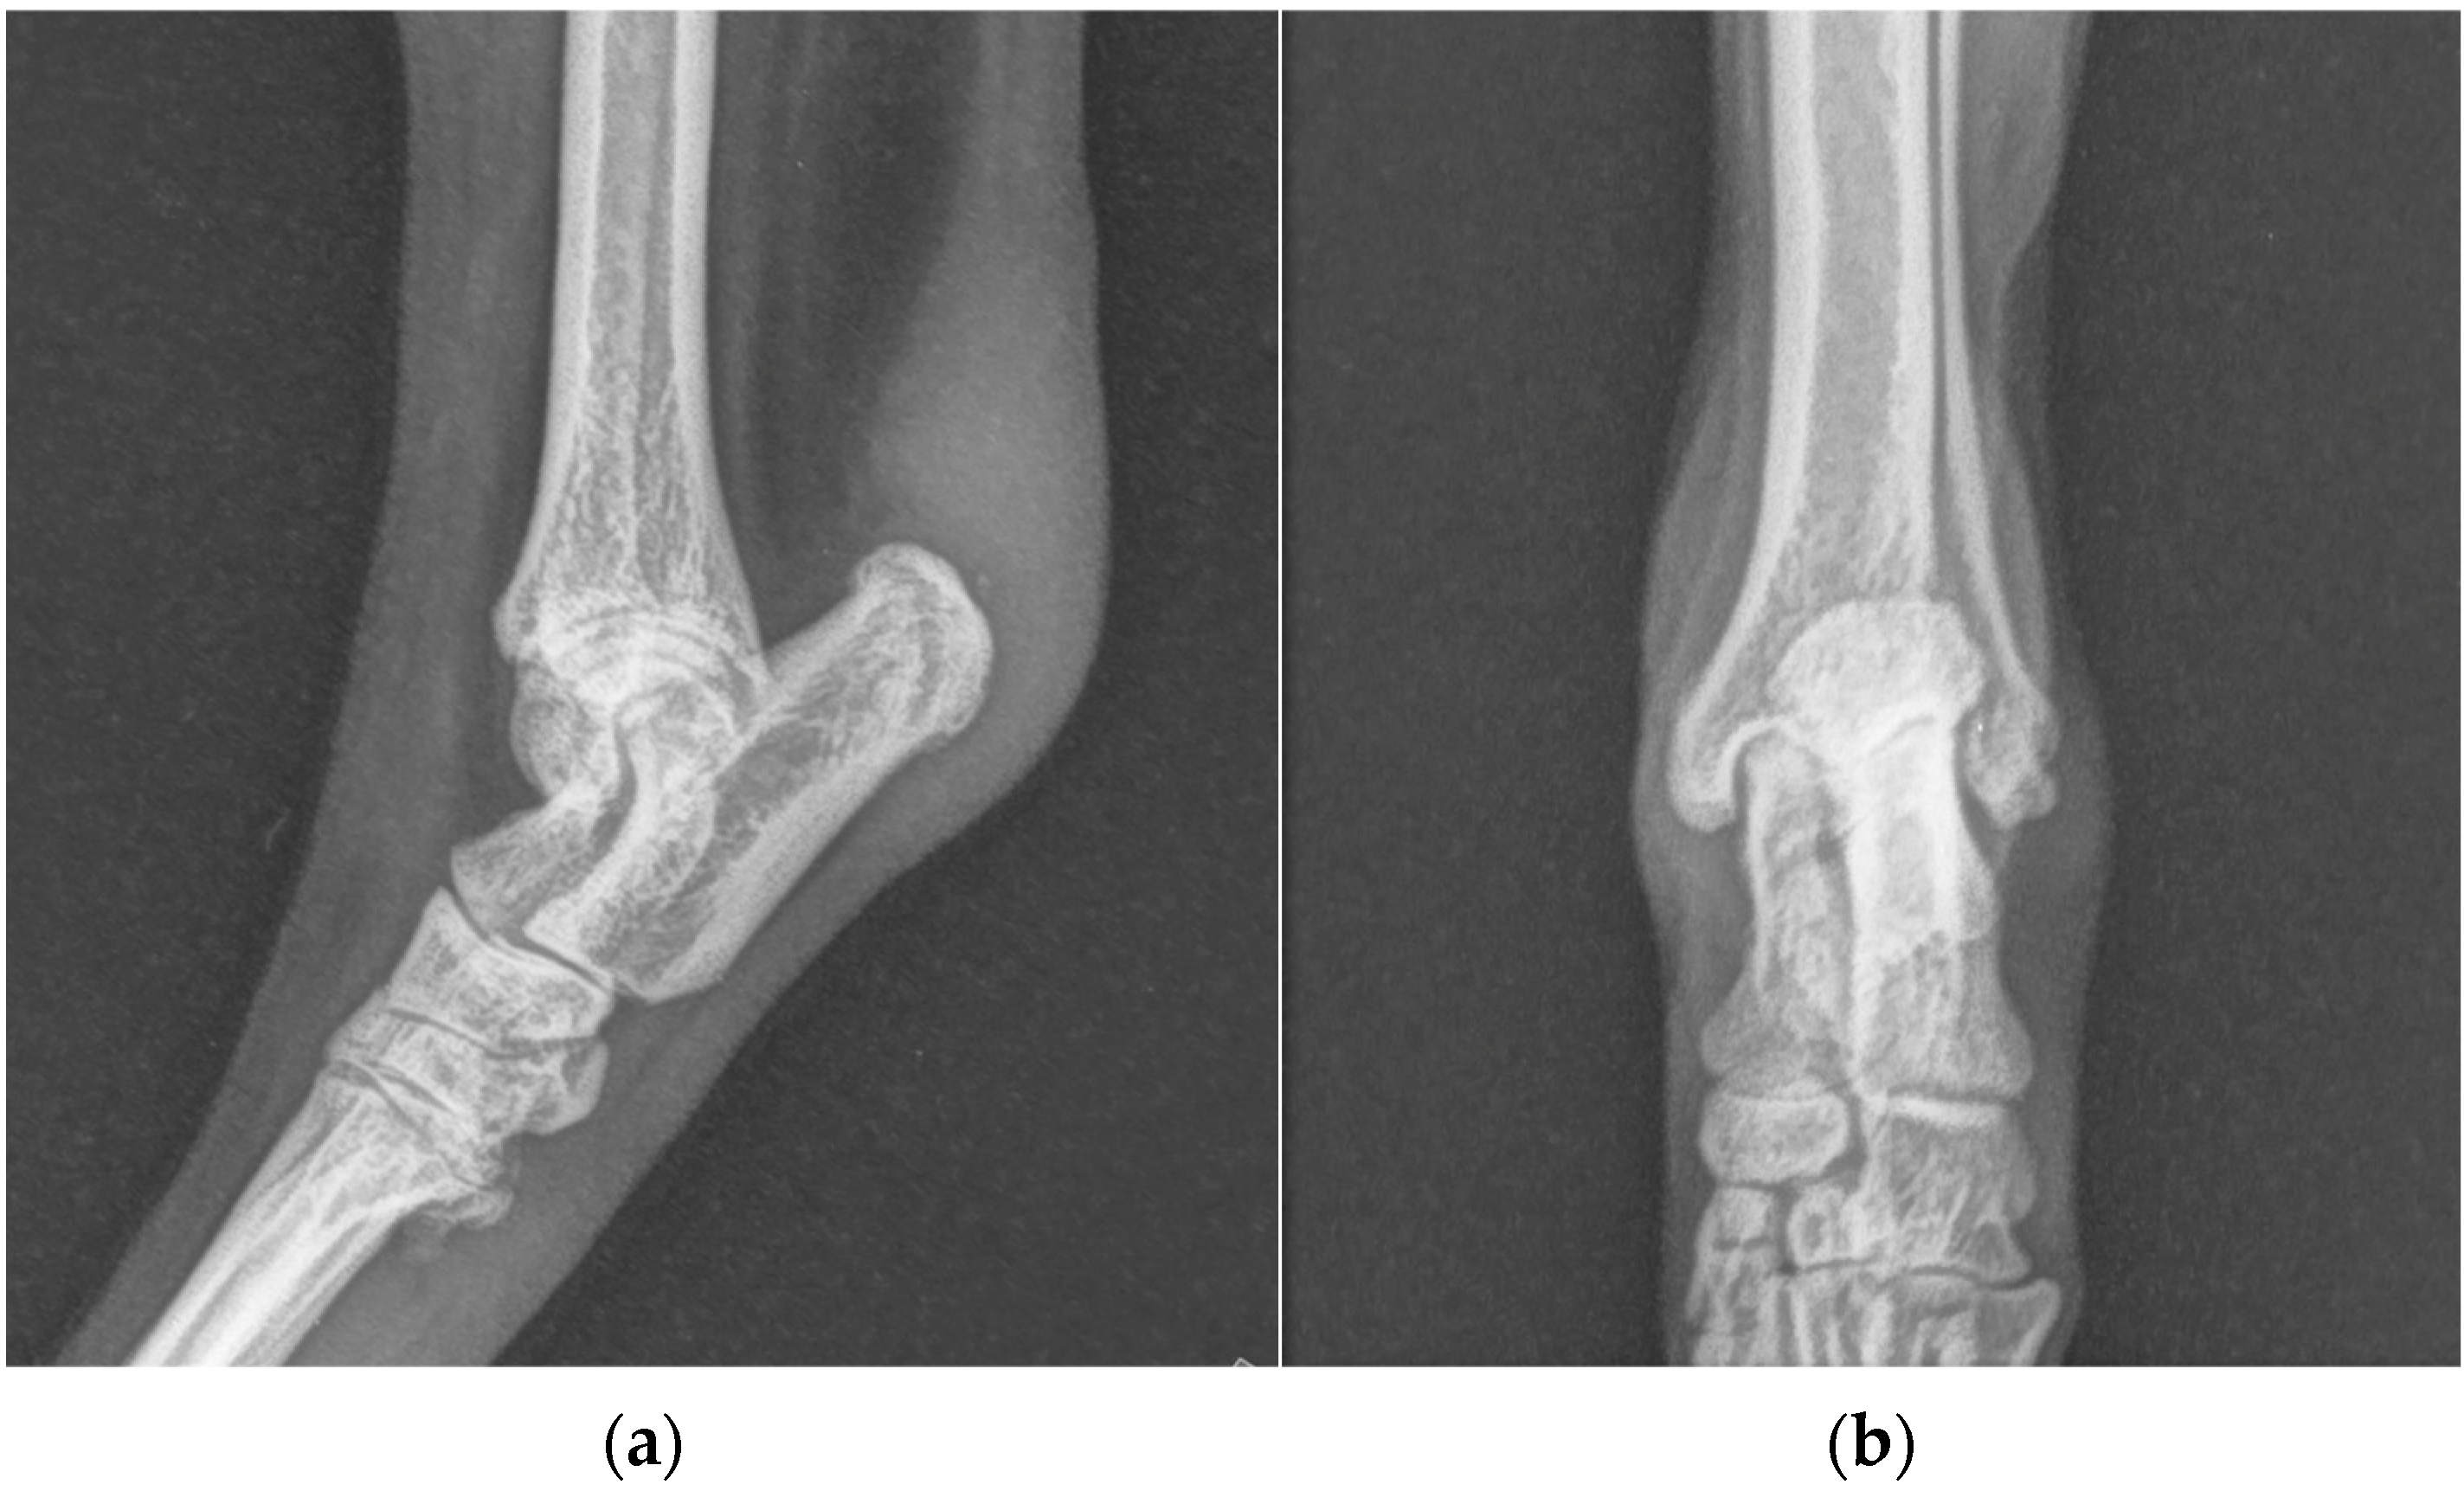

One years after surgery, the patient was presented with the same clinical evidence in the right hind limb (grade II) [19]. SDF tendon lateral luxation of the right hind limb was diagnosed following a clinical and radiographic examination similar to the previous one (Figure 2). The SDF tendon of the left hind limb was perfectly in place, and dorsoplantar and mediolateral radiographic images of the tibial-tarsal joint did not detect mild radiopacity of pericalcaneal soft tissue and rearrangement of bone tissue at the tip of the calcaneal tuberosity without secondary osteoarthrosis. The dog underwent surgery and postoperative treatment as described previously. At the follow-up clinic and radiographic examination, 4 and 8 weeks and 12 months after the intervention, no complications were reported (Figure 3).

Figure 3. (a) Mediolateral and (b) dorsoplantar radiographic projections of the right tibial-tarsal joint 12 months after the surgery. The images highlighted radiopacity of pericalcaneal soft tissue and rearrangement of bone tissue at the tip of calcaneal tuberosity without secondary osteoarthrosis.